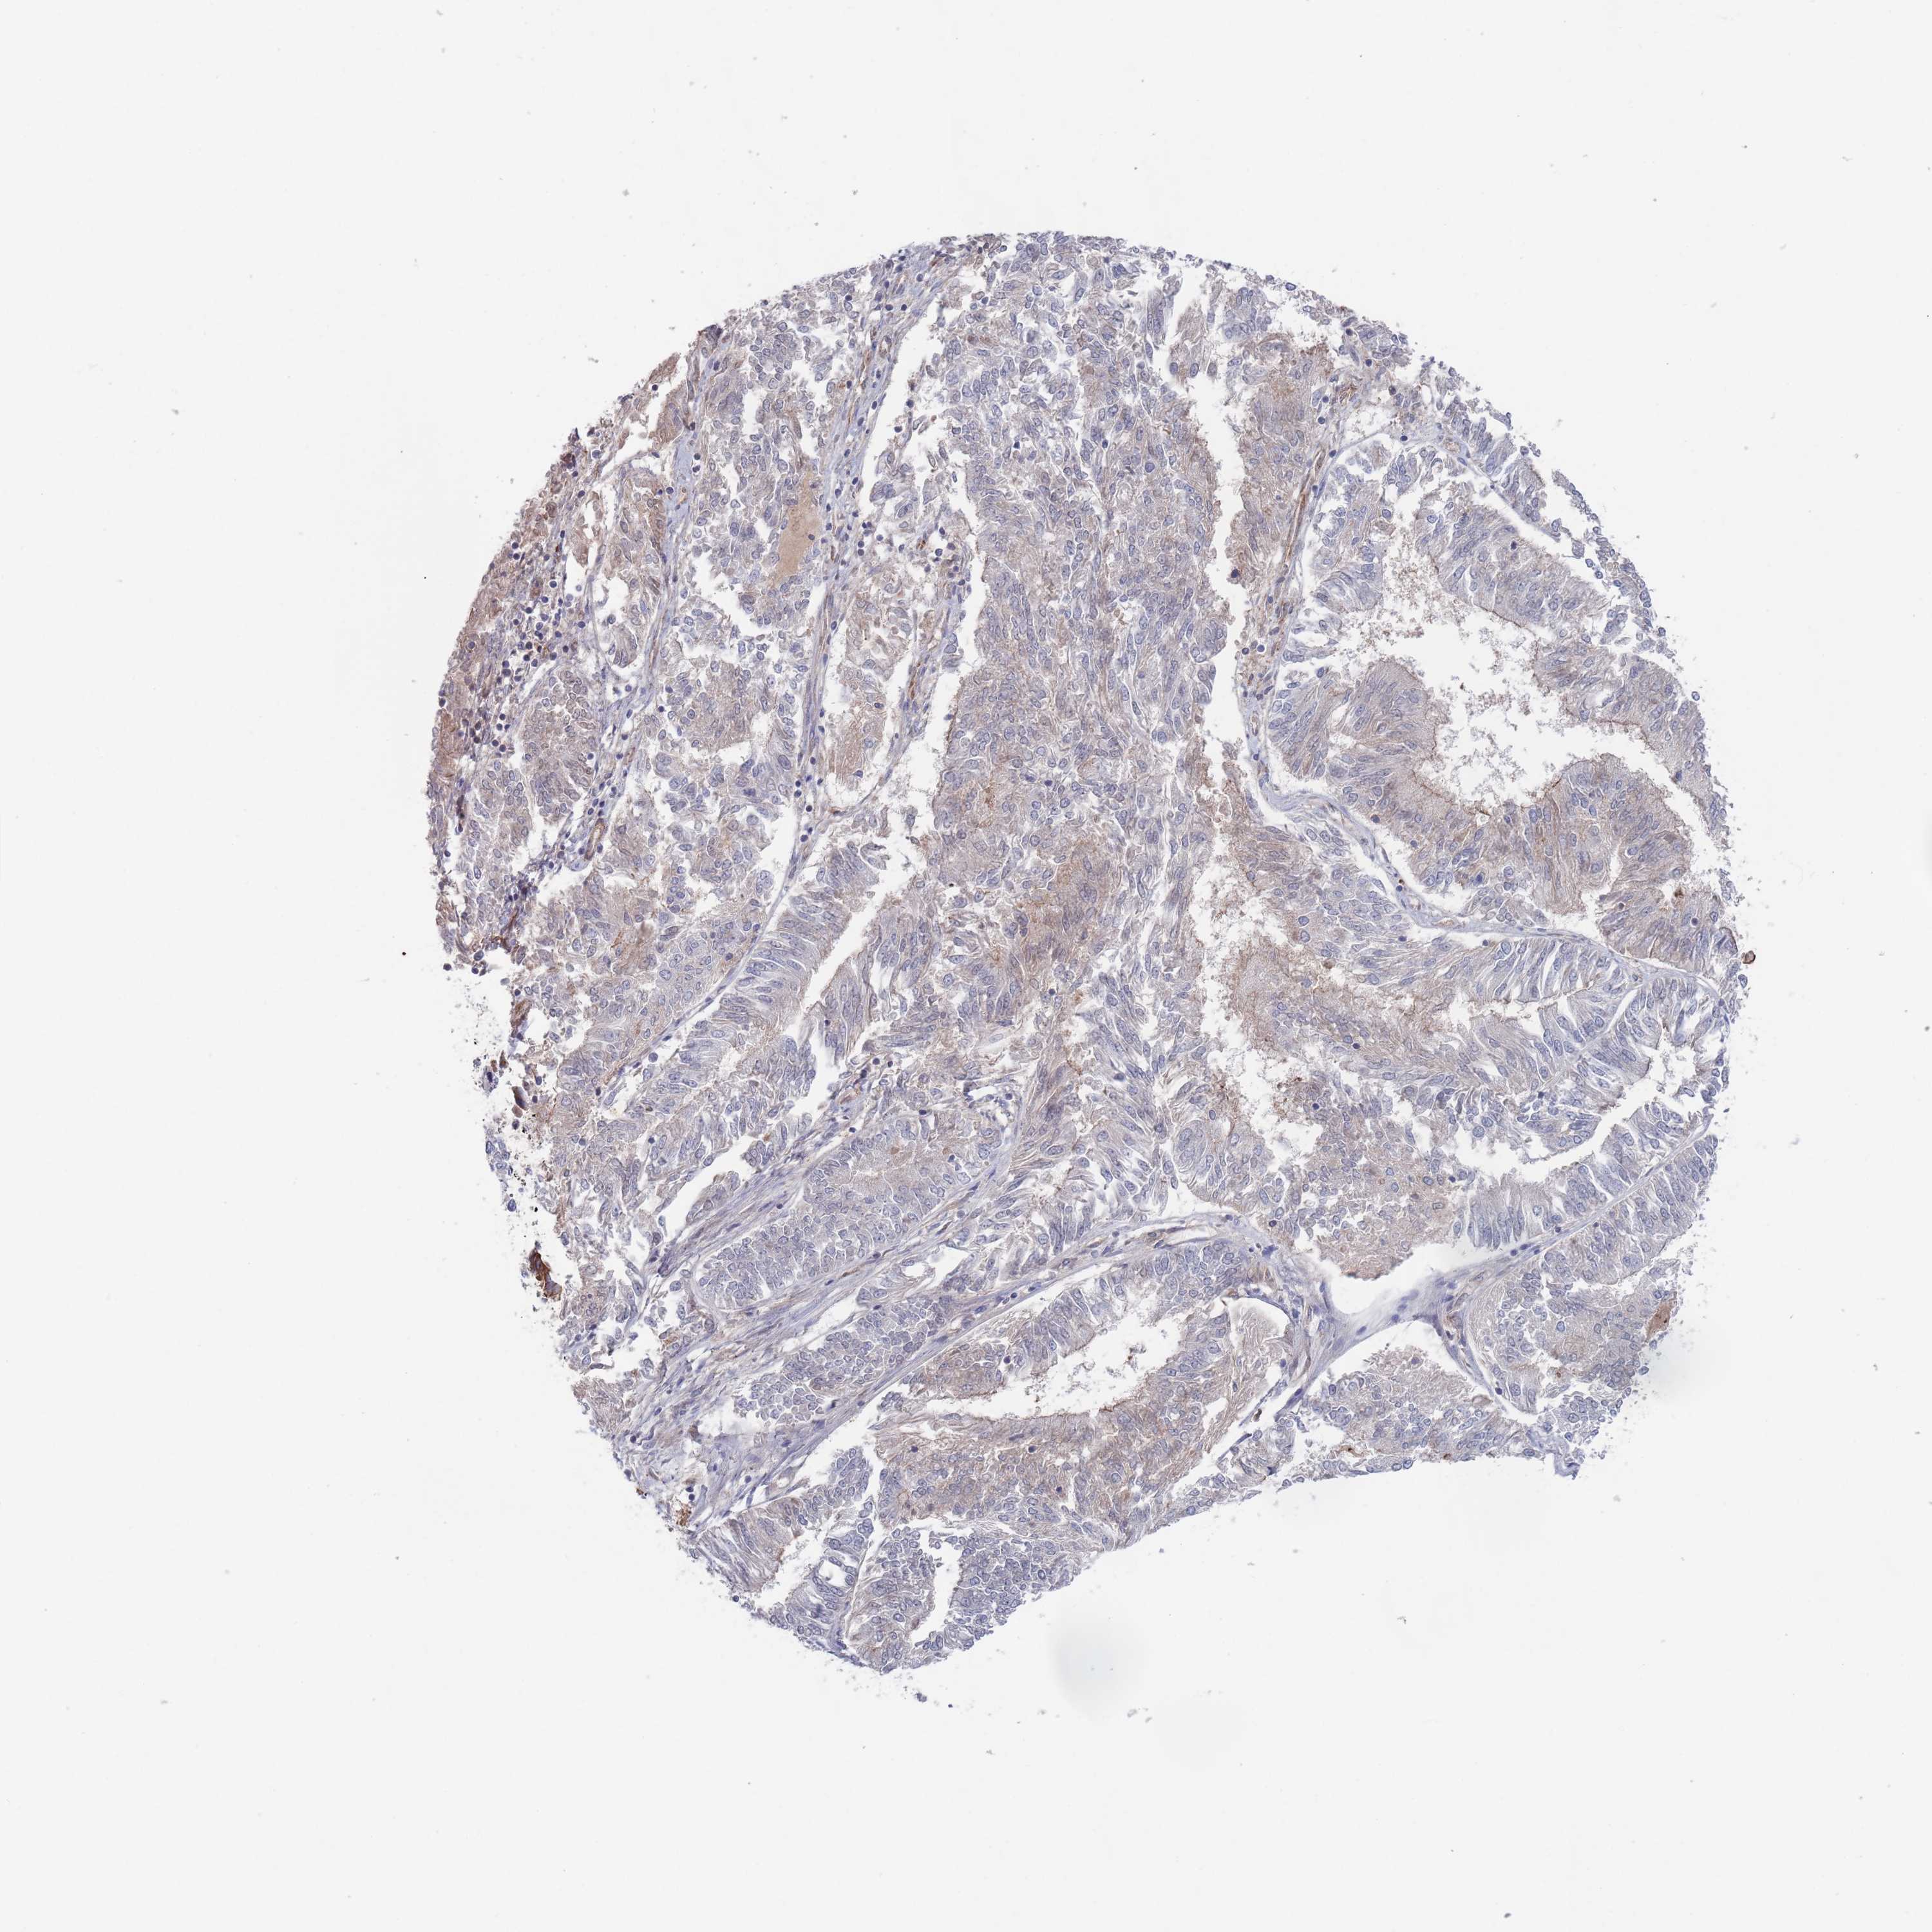

ENDOMETRIAL CANCER - Protein expressioni

A mouse-over function shows sample information and annotation data. Click on an image to view it in a full screen mode. Samples can be filtered based on level of antibody staining by selecting one or several of the following categories: high, medium, low and not detected. The assay and annotation is described here.

Note that samples used for immunohistochemistry by the Human Protein Atlas do not correspond to samples in the TCGA dataset.

Antibody stainingi

Antibody staining in the annotated cell types in the current human tissue is reported as not detected, low, medium, or high, based on conventional immunohistochemistry profiling in selected tissues. This score is based on the combination of the staining intensity and fraction of stained cells.

Each image is clickable and will lead to virtual microscopy that enables deeper exploration of all samples and also displays staining intensity scores, fraction scores and subcellular localization as well as patient and tissue information for each sample.

Antibody HPA042978

Antibody HPA048473

Staining

High

Medium

Low

Not detected

Intensity

Strong

Moderate

Weak

Negative

Quantity

>75%

75%-25%

<25%

None

Location

Nuclear

Cytoplasmic/membranous

Cytoplasmic/membranous,nuclear

Adenocarcinoma, NOS